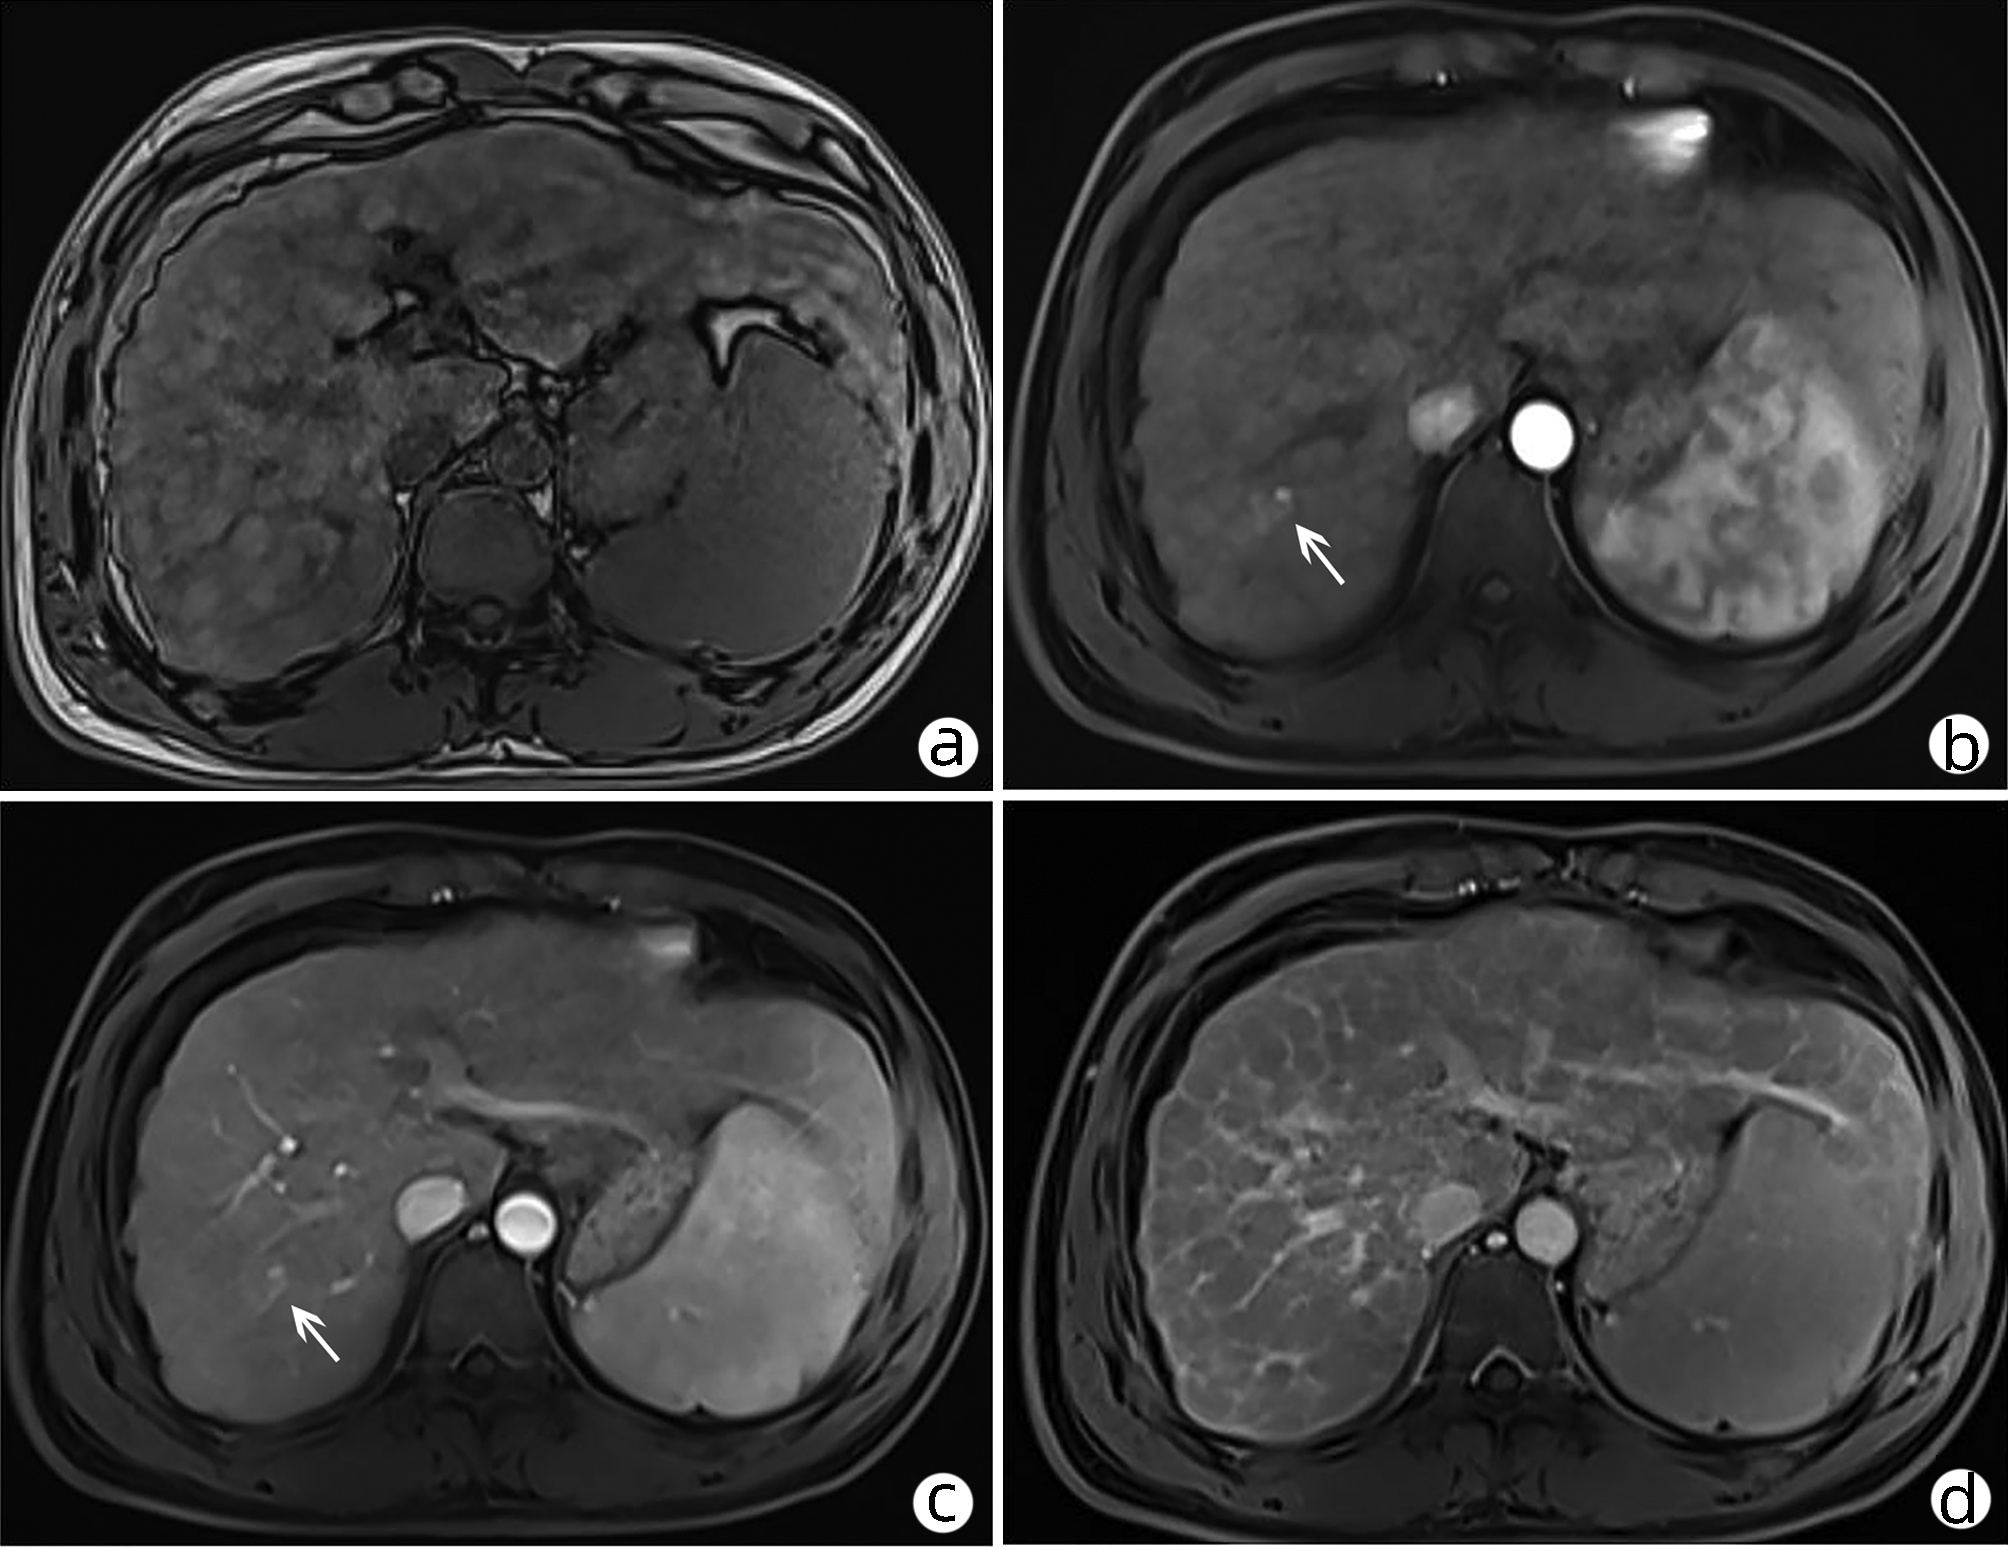

Hepatic paragonimiasis diagnosed by liver histopathology: A case report

Yang LIU, Zhaoxia LI, Tong WU, Jiahe SHI, Ge YU, Guijie XIN

2022, 38(5): 1116-1118. DOI: 10.3969/j.issn.1001-5256.2022.05.027

Abstract(846) HTML (456) PDF (2302KB)(53)

Abstract: